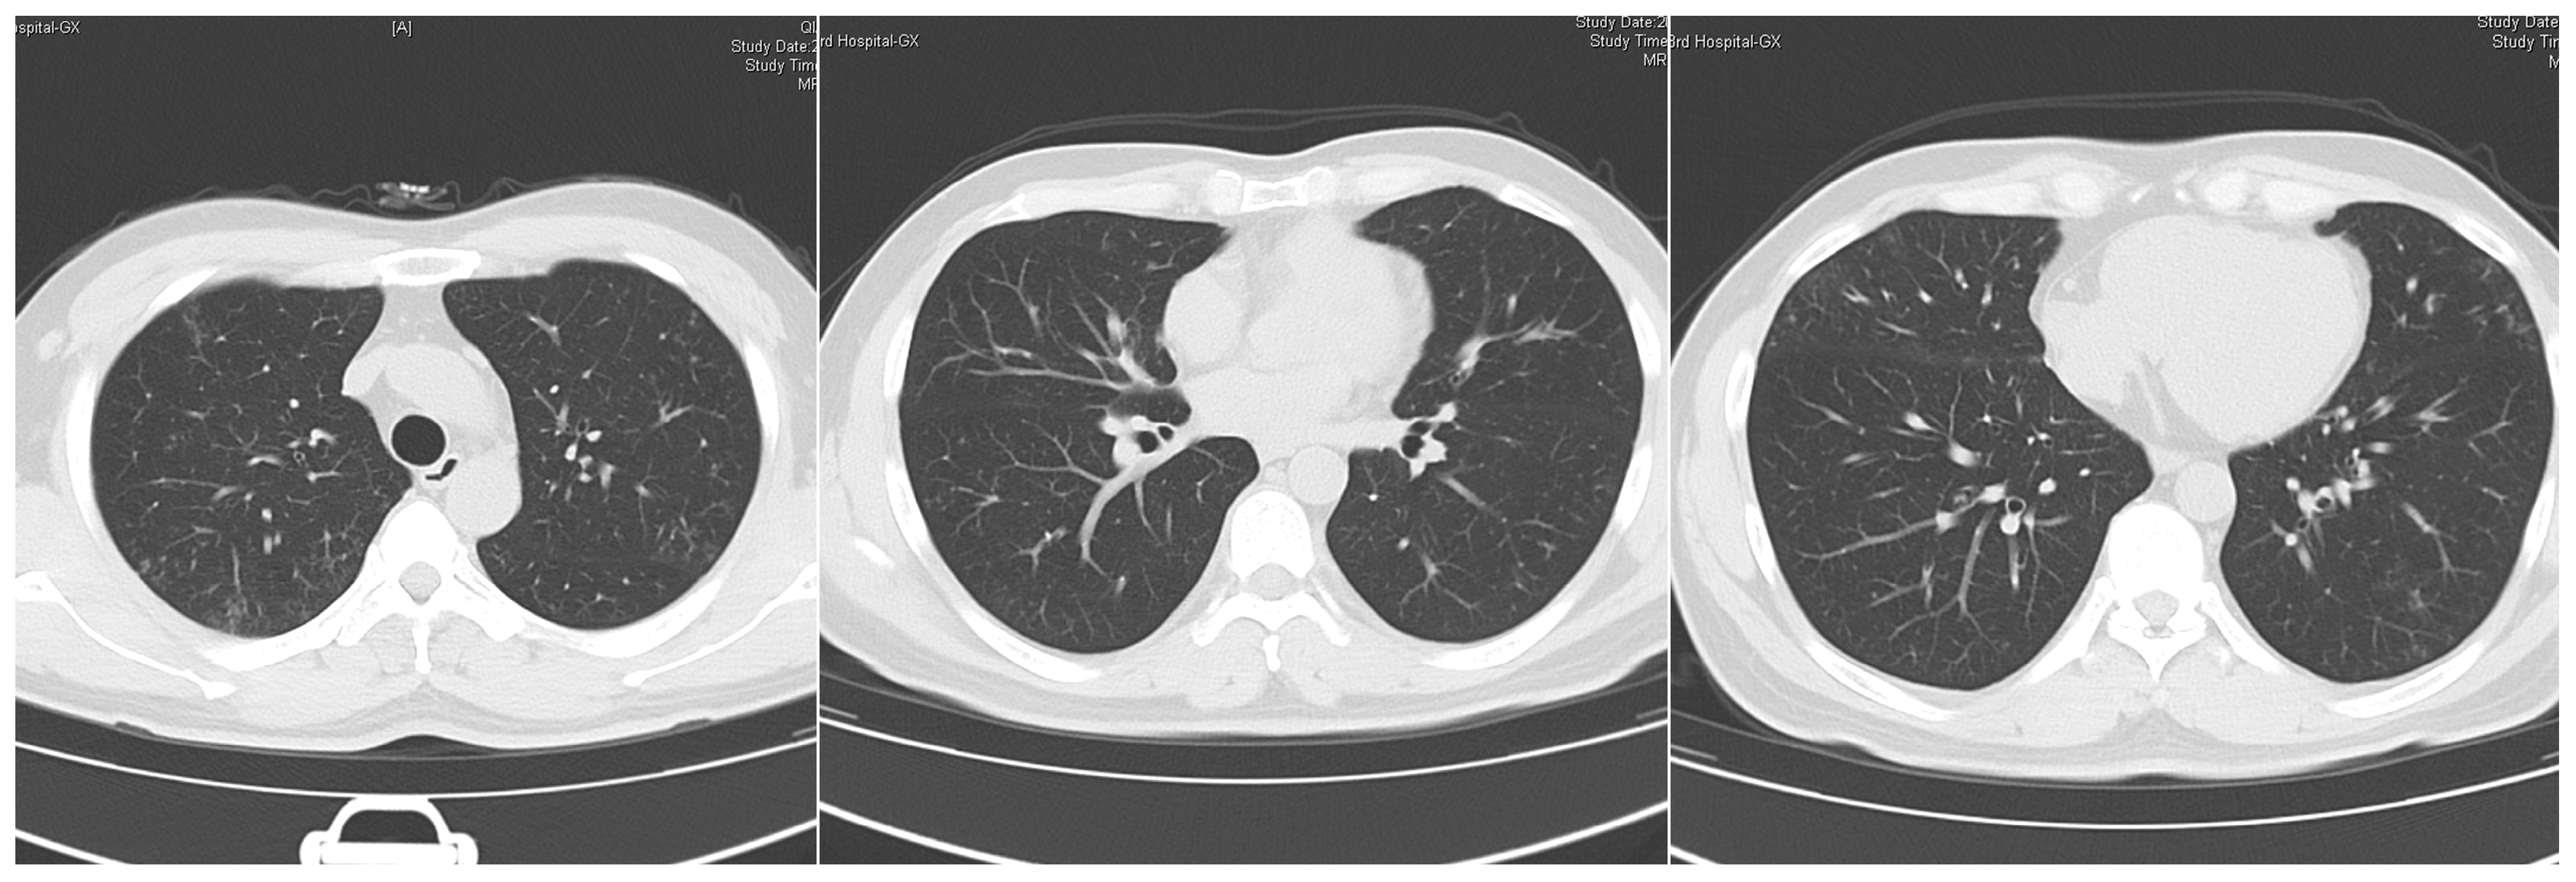

1. Case Presentation